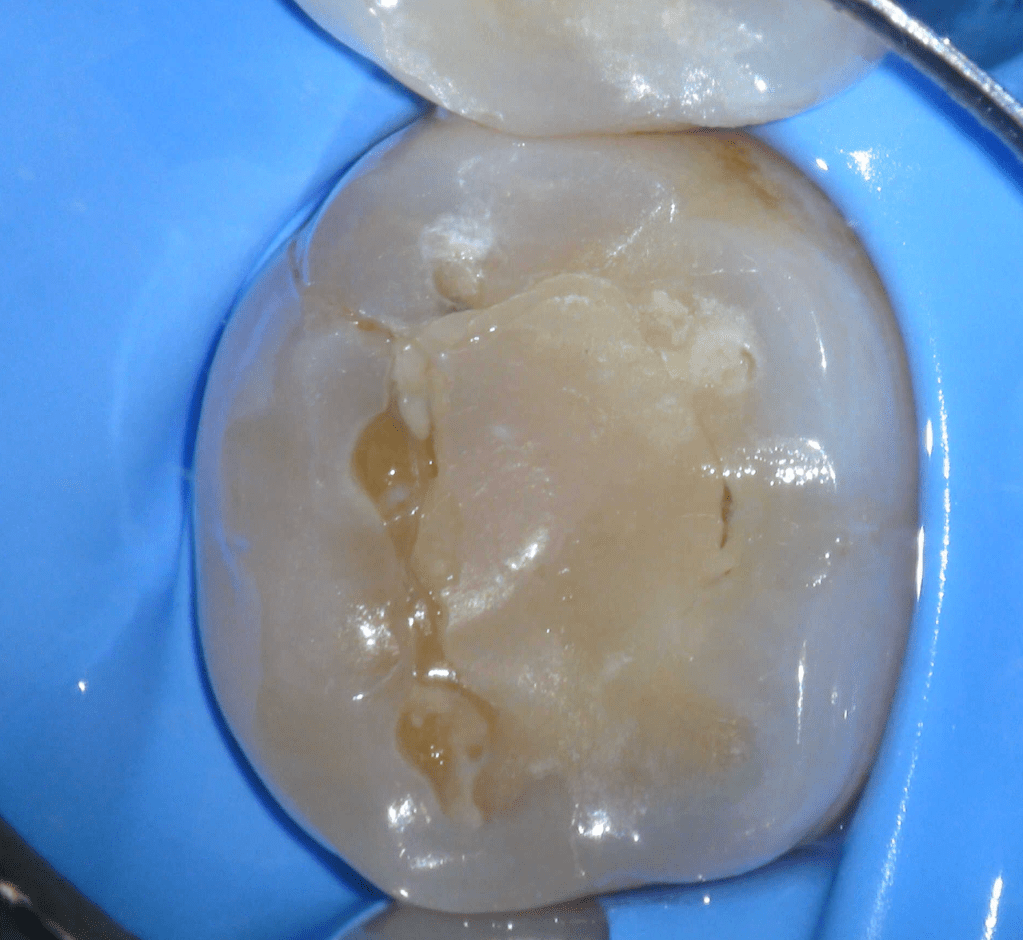

Diagnóstico de fisuras y fracturas

Fisura, remoción amalgama para explorar

Fractura cuspídea tratable